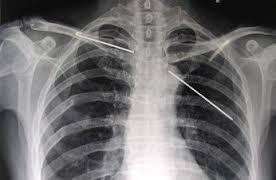

由于锁骨邻近胸膜的顶部和上肺叶,移位的锁骨骨折可造成气胸及血胸。合并气胸的发生率可高达30%。

锁骨骨折不愈合较为少见。锁骨骨折不愈合多见于成年人,中1/3约占75%,外1/3不愈合者约占25%。一般认为伤后4~6个月,临床及X线像未能达到正常的骨折愈合进程,即诊断为骨折不愈合。